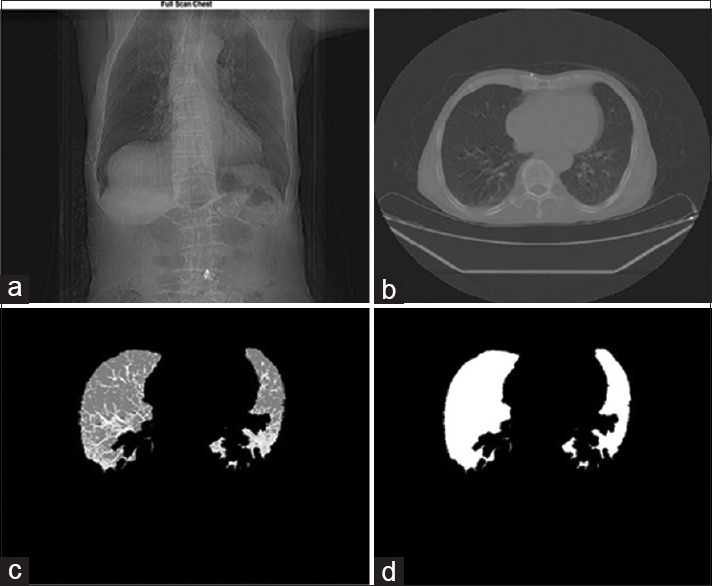

The latest World Health Organization statistics show that the number of people living with COVID-19 disease is now more than 42 million worldwide. Some diagnosis methods include detecting and observing clinical symptoms associated with the disease (fever, dry cough, shortness of breath, sore throat, and muscle fatigue). Some other methods, such as computed tomography (CT)-scan imaging from the lungs, are the more accurate diagnostic methods. In this study, we examine the types of abnormal COVID-19 can cause in the lungs of infected subjects and detect and classify this disease. In this paper, we used data from the lung's CT-scan images from the 79 participants. To do this, in this article, for processing CT-scan images of the lungs to diagnose and classification of the COVID-19 disease in men and women of different ages, for rapid diagnosis and high accuracy of this disease by the automatic classification algorithm is used. The final results showed that the proposed method could base on different categories (gender, age categories, and type of damage caused by COVID-19) with high detection and classification accuracy. The algorithm presented in this article has accurately identified the data of healthy subjects and patients with coronavirus.